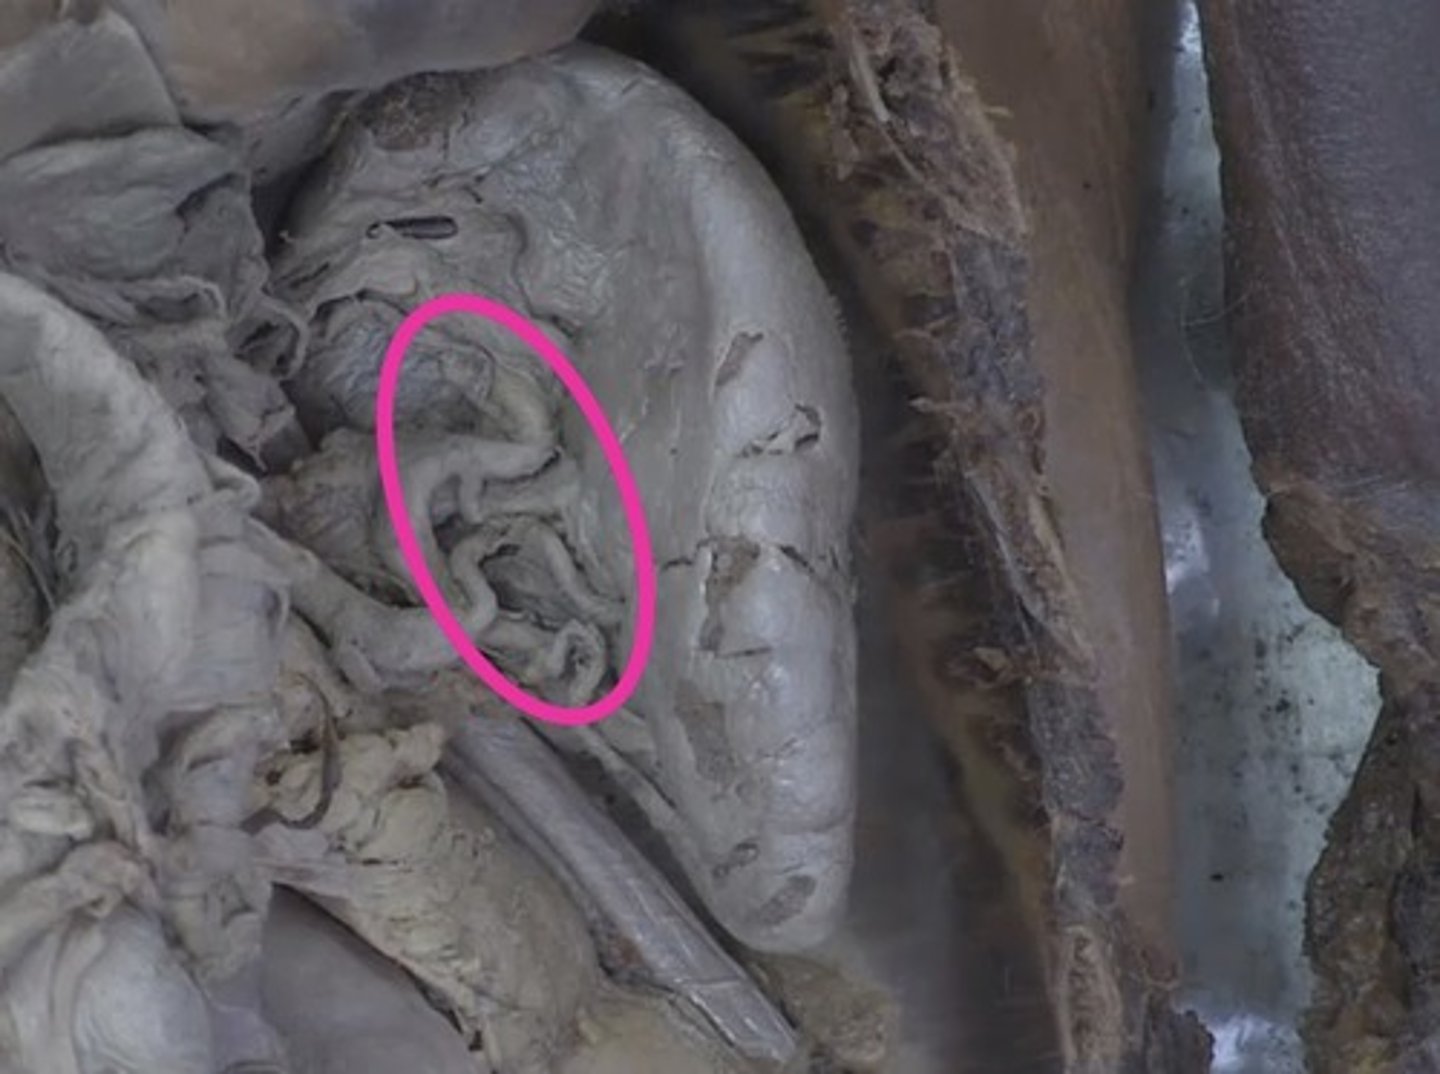

appendix